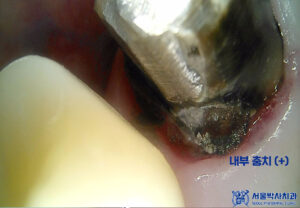

먼저 기존 크라운 제거 후

내부를 확인해 보니

전체적으로 충치가 심하여

발치를 진행하였습니다.

발치 후 아물 동안

아래 임플란트 보철 작업을

시작하였습니다.